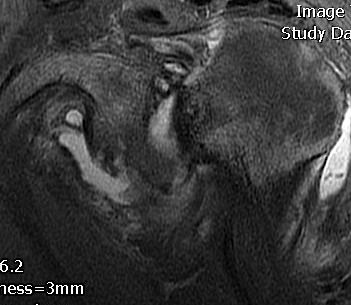

MRI

Acute MRI demonstrating reverse Hill Sachs and posterior labral tear

Chronic posterior shoulder dislocation with humeral head remodelling and glenoid bony deficiency